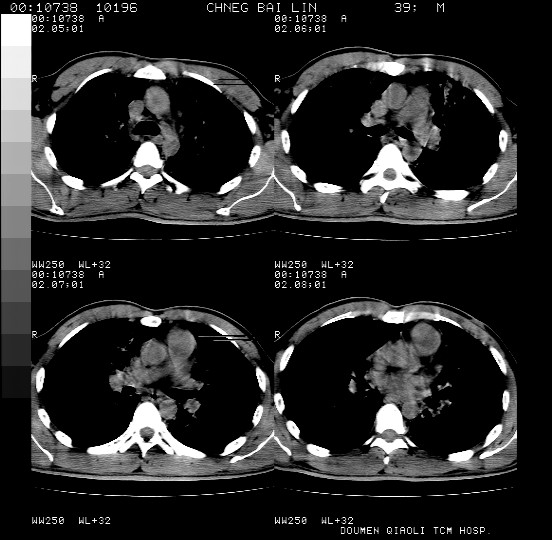

男,39岁。10天前自觉感冒,曾输液一次内容不详曾有吸毒史。现有咳嗽、咳痰胸闷。

双肺弥漫性网状、磨玻璃样病灶,边界不清。有吸毒史。首先考虑机遇性肺部感染。

双肺野蜂窝状结构及多发斑片状影,高度怀疑卡氏囊虫性肺炎

两肺弥漫分布的网状毛玻璃状阴影,边缘模糊不清,纵隔未见明显淋巴结肿大

诊断:机遇性肺部感染